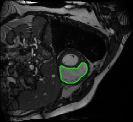

4.3 Comparison with cardic MR images for right ventricle segmentation

Cardiac MRI images often suffer from intensity inhomogeneity due to the varying magnetic susceptibility of cardiac tissues. This can lead to ambiguous boundaries, making it hard for models to consistently identify the left ventricle. Moreover, the heart is composed of several complex anatomical structures, including chambers, valves, and surrounding tissues. Accurately delineating the borders between these various components can be difficult, especially when they are closely positioned or exhibit similar intensity characteristics. In this section, we demonstrate the effectiveness of the RefLSM in segmenting cardiac MR images. The cardiac MR images are standardized to a size of . To enhance the credibility of the proposed model, we segmented 5 cardiac MR images compared the results with 6 other models, including the ALF [MA2019201], LoGRSF [DING2017224], ABC [WENG2021115633], RESLS[8765635], ICTM [WANG2022108794] and FeaACM [XUE2024110673] models. Fig. 5 displays the partial results from all the segmentation models. It is clear that the segmentation results from the RefLSM closely align with the ground truth of the left ventricle segmentation. However, the ALF model demonstrates relatively poor ability to capture the overall structure of the left ventricle; it exhibits limitations with precise boundary detection, particularly in areas of intensity inhomogeneity. Consequently, the evolution curve of the ALF fits into an unstable wave-like result. Suffering from intensity inhomogeneity and surrounding anatomical structures, the LoGRSF model, ABC model and RESLS model all represent over-segmentation and under-segmentation to some extent. Additionally, the results in the 6th column of Fig. 5 show multiple instances where where the ICTM model inaccurately identifies adjacent myocardial tissues as part of the left ventricle due to their similar intensity, leading to false positives. While the FeaACM demonstrates some ability to segment the left ventricle, it is not robust and fails to segment the 5th row of Fig. 5. The 2nd and 3rd rows also include small adjacent excessive regions. In contrast, our proposed model demonstrates marked improvements in accurately capturing the left ventricle’s boundaries. It effectively addresses challenges associated with severe intensity inhomogeneity and noise, resulting in better segmentations. The proposed method appear to maintain better structural integrity in the segmented images, closely aligning with the ground truth.

To quantitatively measure the segmentation results of each model, we compute the Dice and Precision values for left ventricle segmentation. Moreover, we opted for a voilin plot to effectively compare the RefLSM with six other models, as shown in Fig. 7. The results clearly demonstrate that the RefLSM yields superior Dice and Precision values than the other representative models, indicating its closer alignment with the ground truth and highest segmentation accuracy.